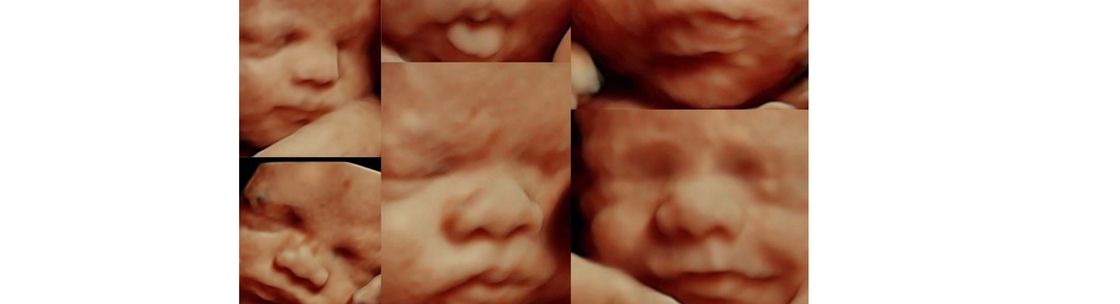

For Blind Moms 3 D Prints Of Fetuses Stand In For Sonogram Images

Kansas 4d Ultrasound